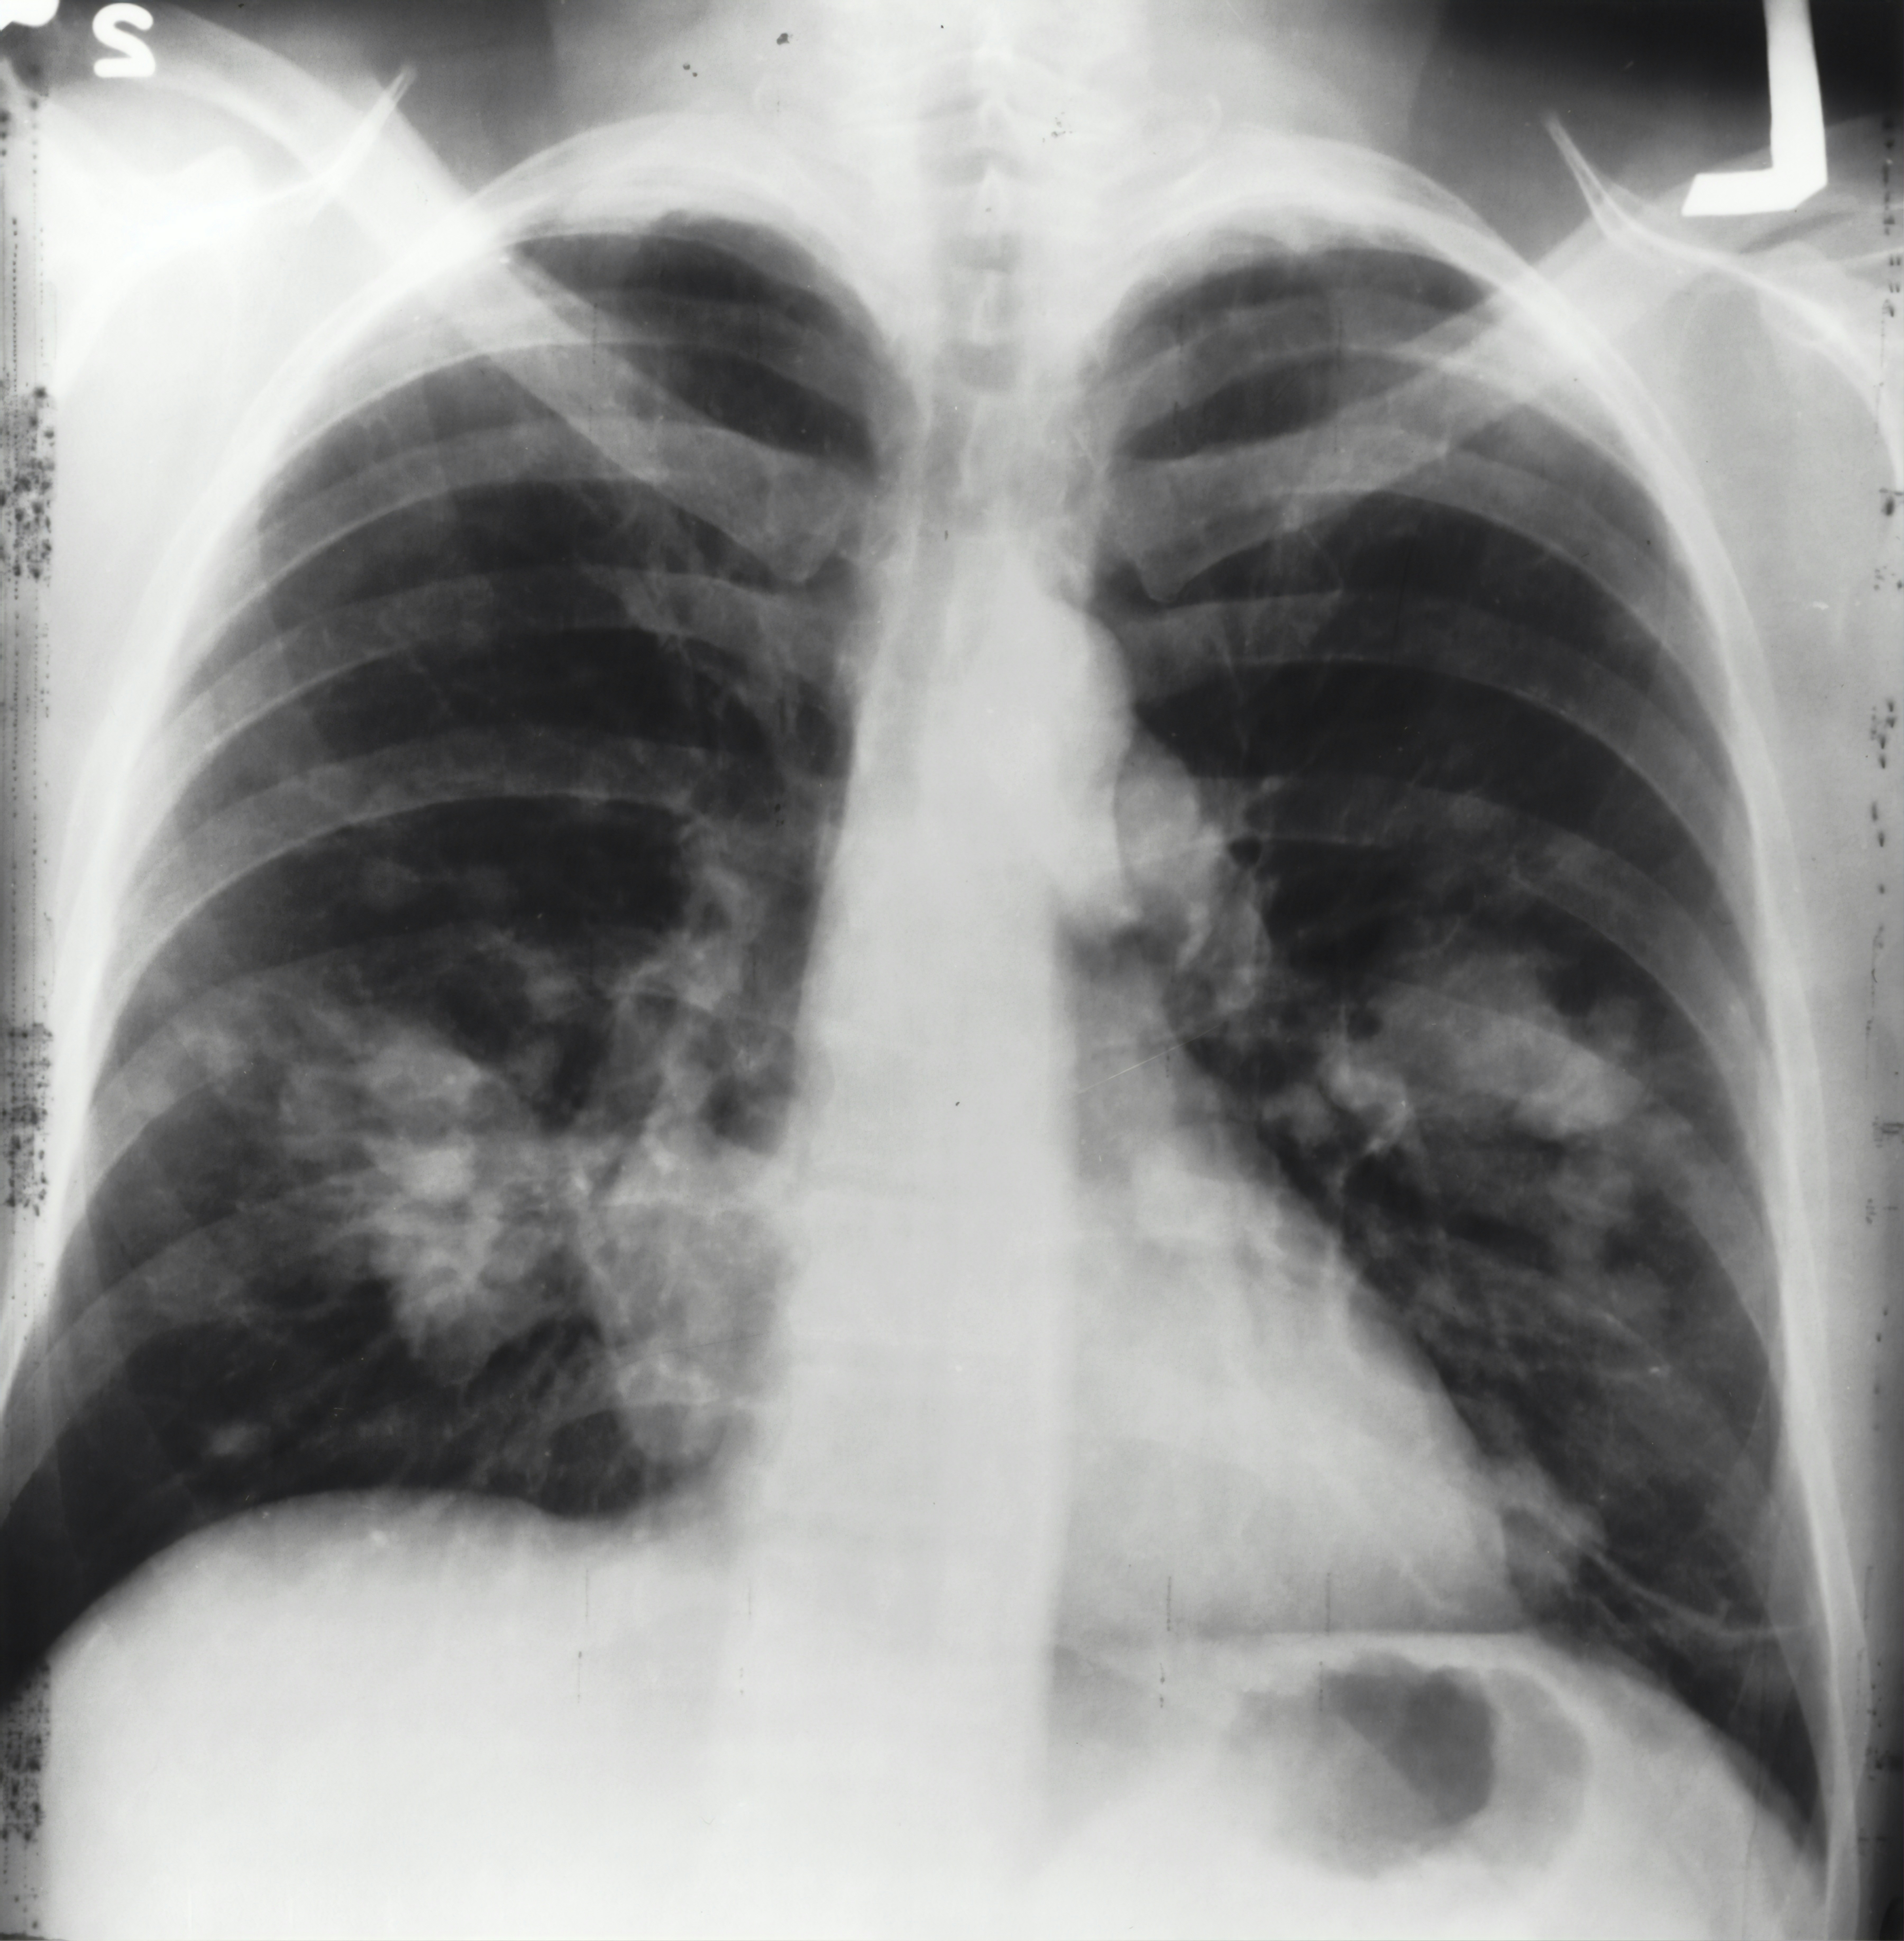

특히 만성폐쇄성폐질환(COPD), 천식, 폐렴 등의 증상이 있는 사람들에게 NAC는 점액 분해 및 산화 스트레스 억제를 통해 증상 완화에 도움을 줄 수 있습니다.

3. 폐 건강과 NAC

폐 건강을 유지하기 위해 가장 중요한 것은 염증과 점액의 적절한 조절입니다. NAC는 점액을 묽게 하고 배출을 돕는 역할을 하여, 기침과 가래를 줄여주는 데 효과적입니다. 특히 흡연자, 미세먼지 노출이 잦은 사람들에게 추천됩니다.